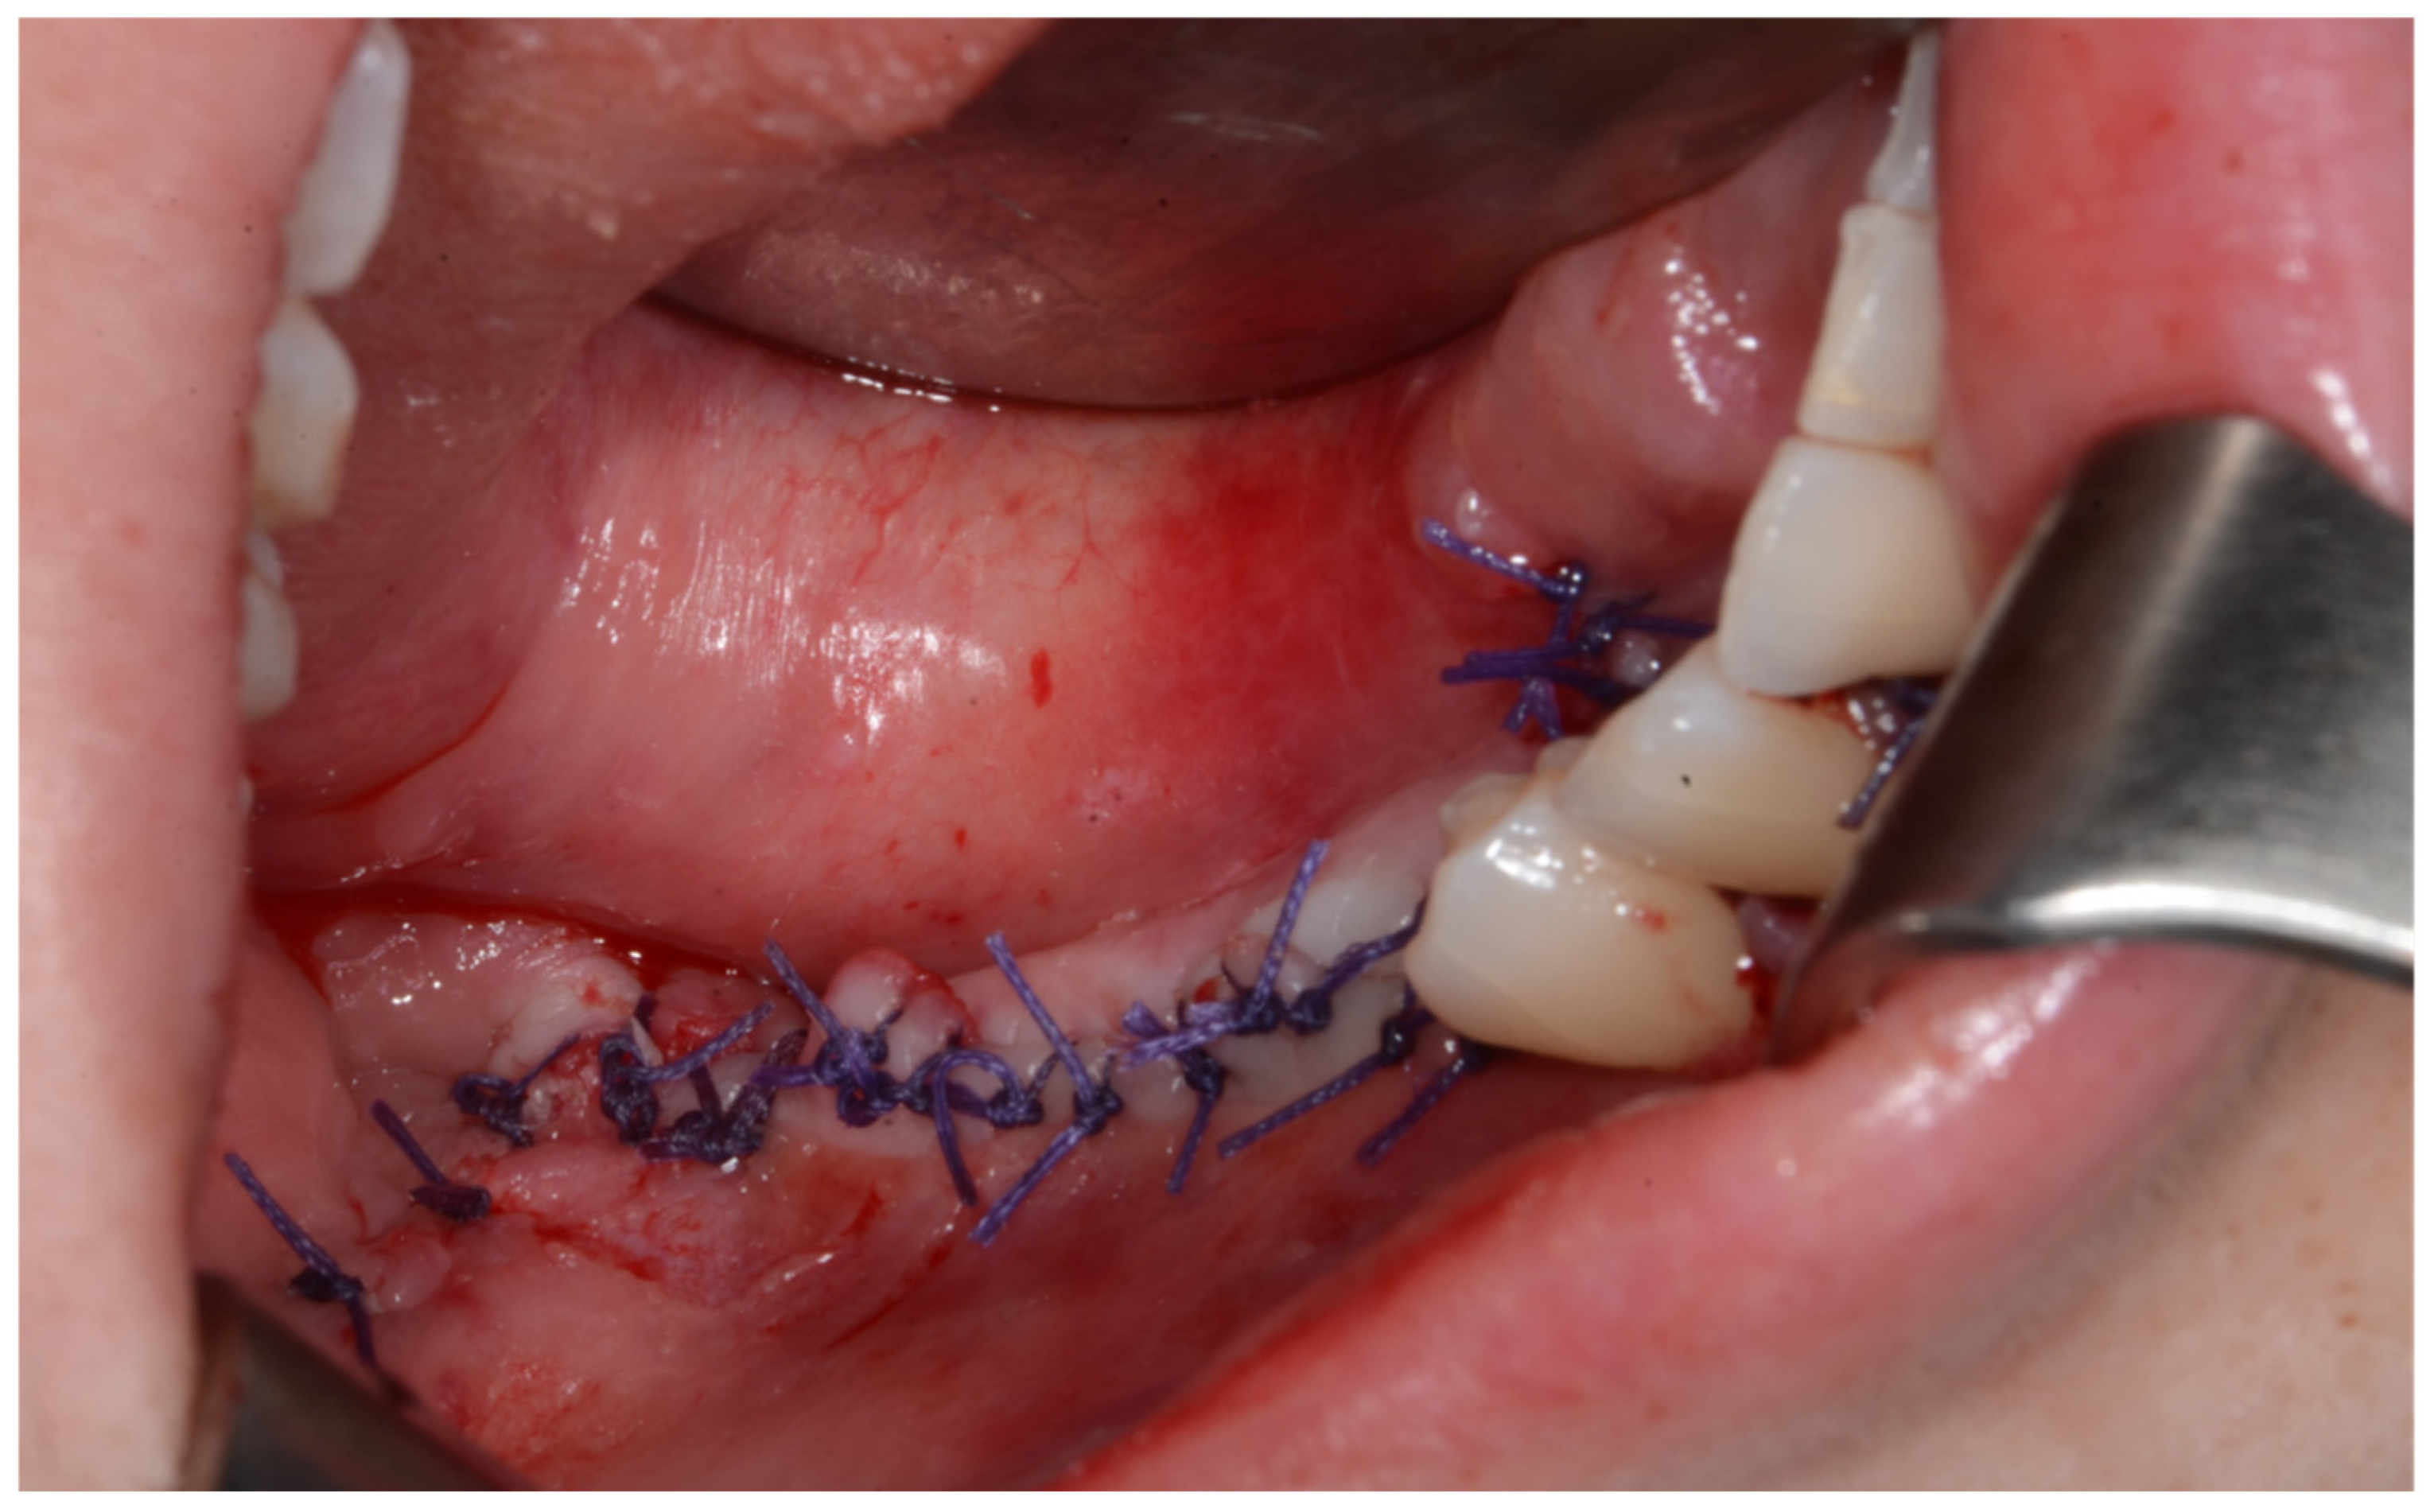

Surgery was performed under general anesthesia. #45, 46, and 47 were extracted. Segmental mandibulectomy was performed using a surgical guide through a submandibular approach. (Figure 6). The left iliac crestal DCIA flap was harvested according to the surgical guide. (Figure 7) To minimize the morbidity of the donor site, the donor site was reconstructed using titanium mesh and allobone chip graft. (Figure 8) Microvascular anastomosis was performed using the facial artery and facial vein. Fixation of the resected mandible and the bicortical iliac bone flap was achieved using a customized reconstruction plate (Cusmedi ©, Sungnam, Republic of Korea) designed to have a thickness of 2 to 3 mm according to the patient’s mandibular morphology and the periphery of the iliac bone flap and 3D printed by the selective laser melting (SLM) method and eight 2.3 mm reconstruction screws. (Figure 9). A silastic drain was inserted into the submandibular region and sutured. (Figure 10) The final diagnosis was ameloblastoma.

After primary closure.